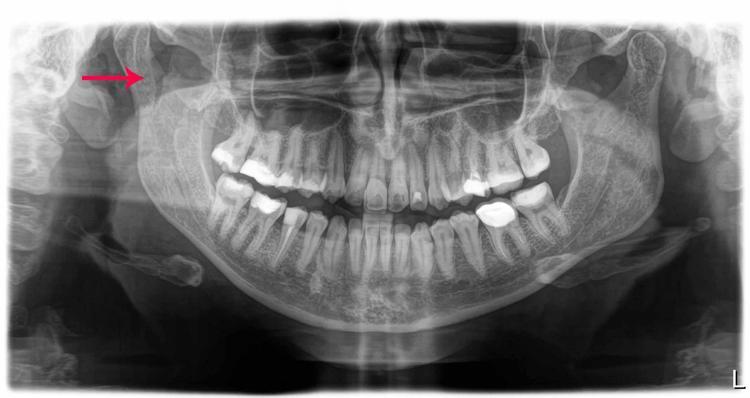

Tekerlek o mazgala girdi. Öne doğru savruldum ve çenemi çarptım. Çenem, burnum, bütün yüzümü yere çarptım. Olayın sıcağıyla başta anlamadım. Çene kemiğim iki taraftan kırılmış. Çok büyük bir cerrahi ameliyat geçirdim. Ameliyat öncesinde dişlerime tel takıldı.

10

Çünkü lastikle çenemi oturtmaları gerekiyordu. Ameliyatın yapıldığı yerden yüz sinirleri geçtiği için, sağ tarafımda yüz sinirlerimde geçici yüz felci oluştu. Gözüm kapanmıyordu, güldüğüm zaman ağzım hareket etmiyordu. Çiğneme, yemek yiyememe bir tarafa, ağrılarım dayanılmazdı. 6-7 ayı buldu iyileşmem. Sağ tarafım, ameliyat sonrası başka bir ben oldu. Bu olaydan sonra uygulamayı hemen sildim ve çevremdeki insanlara da başıma geleni anlatıp kullanmamalarını öneriyorum."